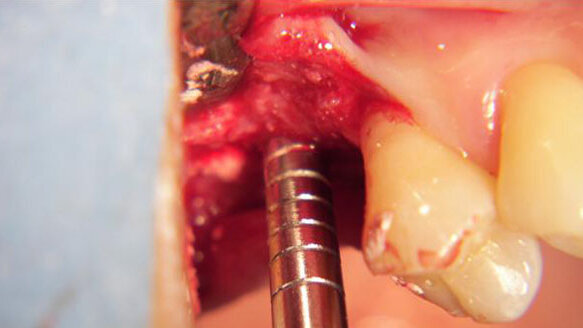

Dopo aver scollato il lembo (Fig. 3) si pratica l’osteotomia fino al di sotto del pavimento del seno mascellare prima con una fresa da 2 e poi da 3 mm (Fig. 4).

Con l’utilizzo del manipolo per chirurgia piezoelettrica (Piezon Master Surgery, EMS) e un inserto a pallina diamantato si perfora il pavimento del seno mascellare. Utilizzando un osteotomo di Summers si zeppa del materiale da innesto di derivazione suina (Gen-Os Osteobiol, Tecnoss) mescolato con gel al collagene (Gel 0 Osteobiol, Tecnoss) (Figg. 5, 6, 7).